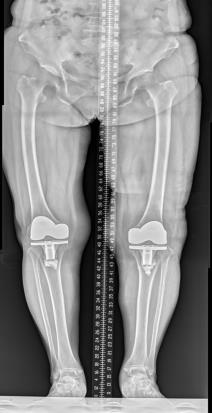

(三)膝骨关节炎全膝关节置换术